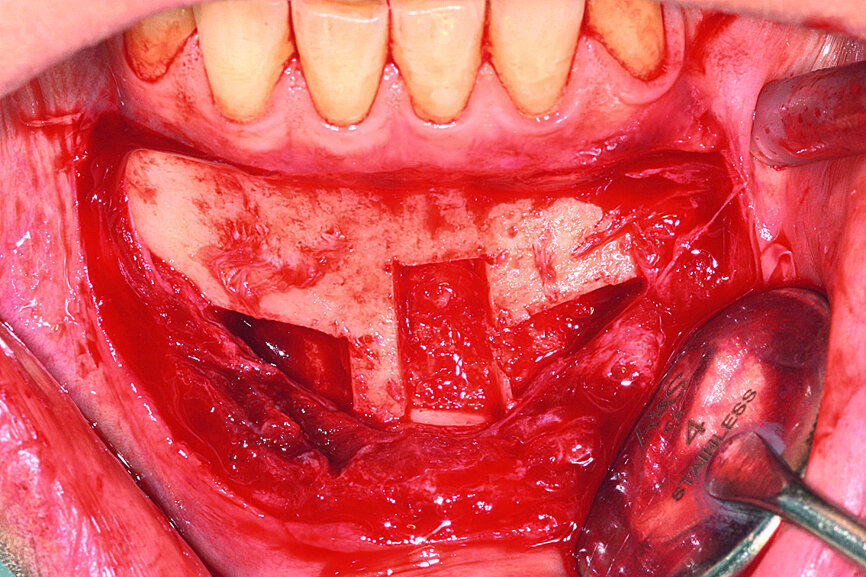

Fig. 6: The grafts were harvested from the chin symphysis and firmly attached by surgical screws in the recipient site.

Fig. 7: The grafts were harvested from the chin symphysis and firmly attached by surgical screws in the recipient site.

Bone graft

Anaesthetic was administered in the maxillary and mandibular anterior region. For the mandible, the sample was taken from the cortical bone and a section of the cancellous bone by piezoelectric surgery. The grafts were harvested from the chin symphysis, as close as possible to the mandibular inferior ridge to avoid disturbing the incisor’s sensitive innervation, which can be a frequent complication of the procedure. The vestibular cortical bone scar was perforated with a small round bur, allowing for rapid revascularisation of the grafts. The grafts were then positioned and secured in place with mini-screws (Figs. 6 & 7).

To increase success, a blood sample was taken and centrifuged according to the Choukroun platelet-rich fibrin (PRF) technique [5] in order to recuperate the fibrin clots. The clots were compressed between two compresses to evacuate the serum and to form the membranes which were then applied to the surgical site and in the mandibular harvesting sites (Figs. 8 & 9).